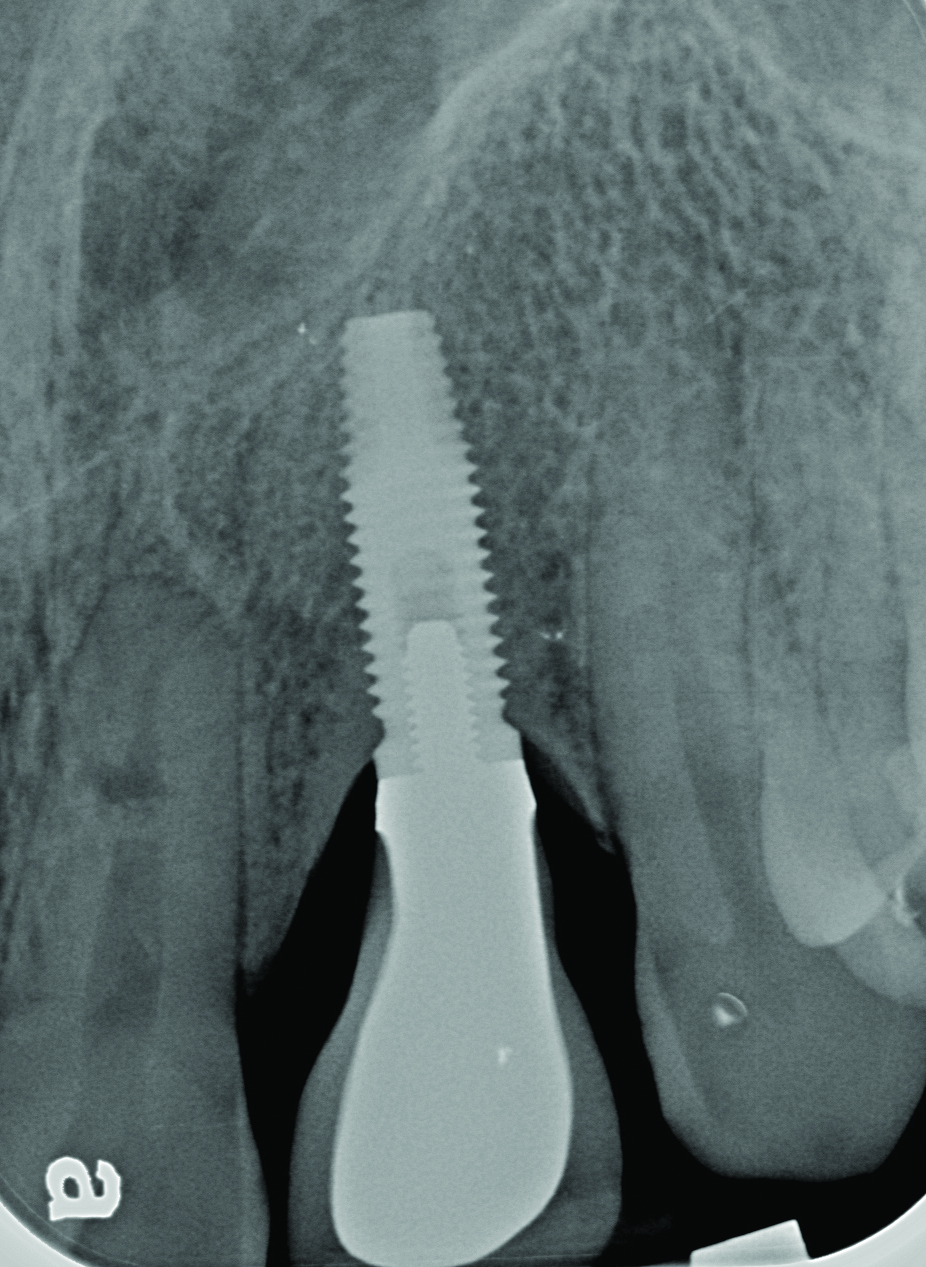

Radiograph of the area suggests moderate to advanced bone loss at the mesial aspect making the diagnosis peri-implantitis.

Figure 4